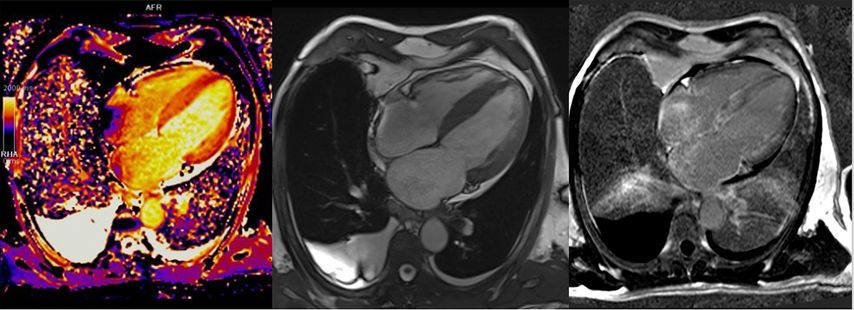

Über die Bestimmung des extrazellulären Volumens (ECV) kann außerdem der Verdacht auf eine Speichererkrankung erhärtet werden (Abb.4). Auch seltene Erkrankungen wie M.Fabry haben charakteristische Befundkonstellationen im kardialen MRT (Tab.1).12

Abb. 4:Kardiale MRT bei ATTR-Amyloidose: erhöhtes T1-Mapping (links), 4-Kammer-Bick mit Hypertrophie (Mitte), diffuses subendokardiales LGE (rechts)